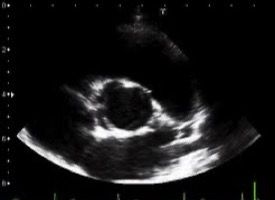

Sezioni Parasternali

Sezioni Apicali

Sezioni Sottocostali